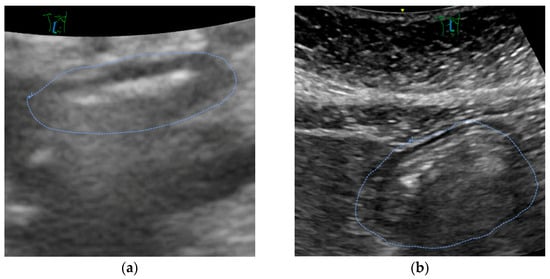

Figure 2 shows the antral cross-sectional area of patients before and after the implementation of the liberal fluid fasting concept and reveals only a slight increase in gastric content.

Mostly, ultrasound revealed an empty stomach (Figure 3a). In some patients, we found proof that tablets were taken in the morning or immediately before the call for theatre. Only in a small number of patients, remnants of clear liquids were documented (see Figure 3b). No solids were encountered.

Figure 3. Screenshot of a representative gastric ultrasound exam performed in a patient (a) with an empty stomach (CSA 2.98 cm−2 corresponding to a calculated gastral volume of 70.5 mL) and (b) with a full stomach (CSA 12.0 cm2, 202 mL). Both patients had no liquids for more than two hours before the exam.